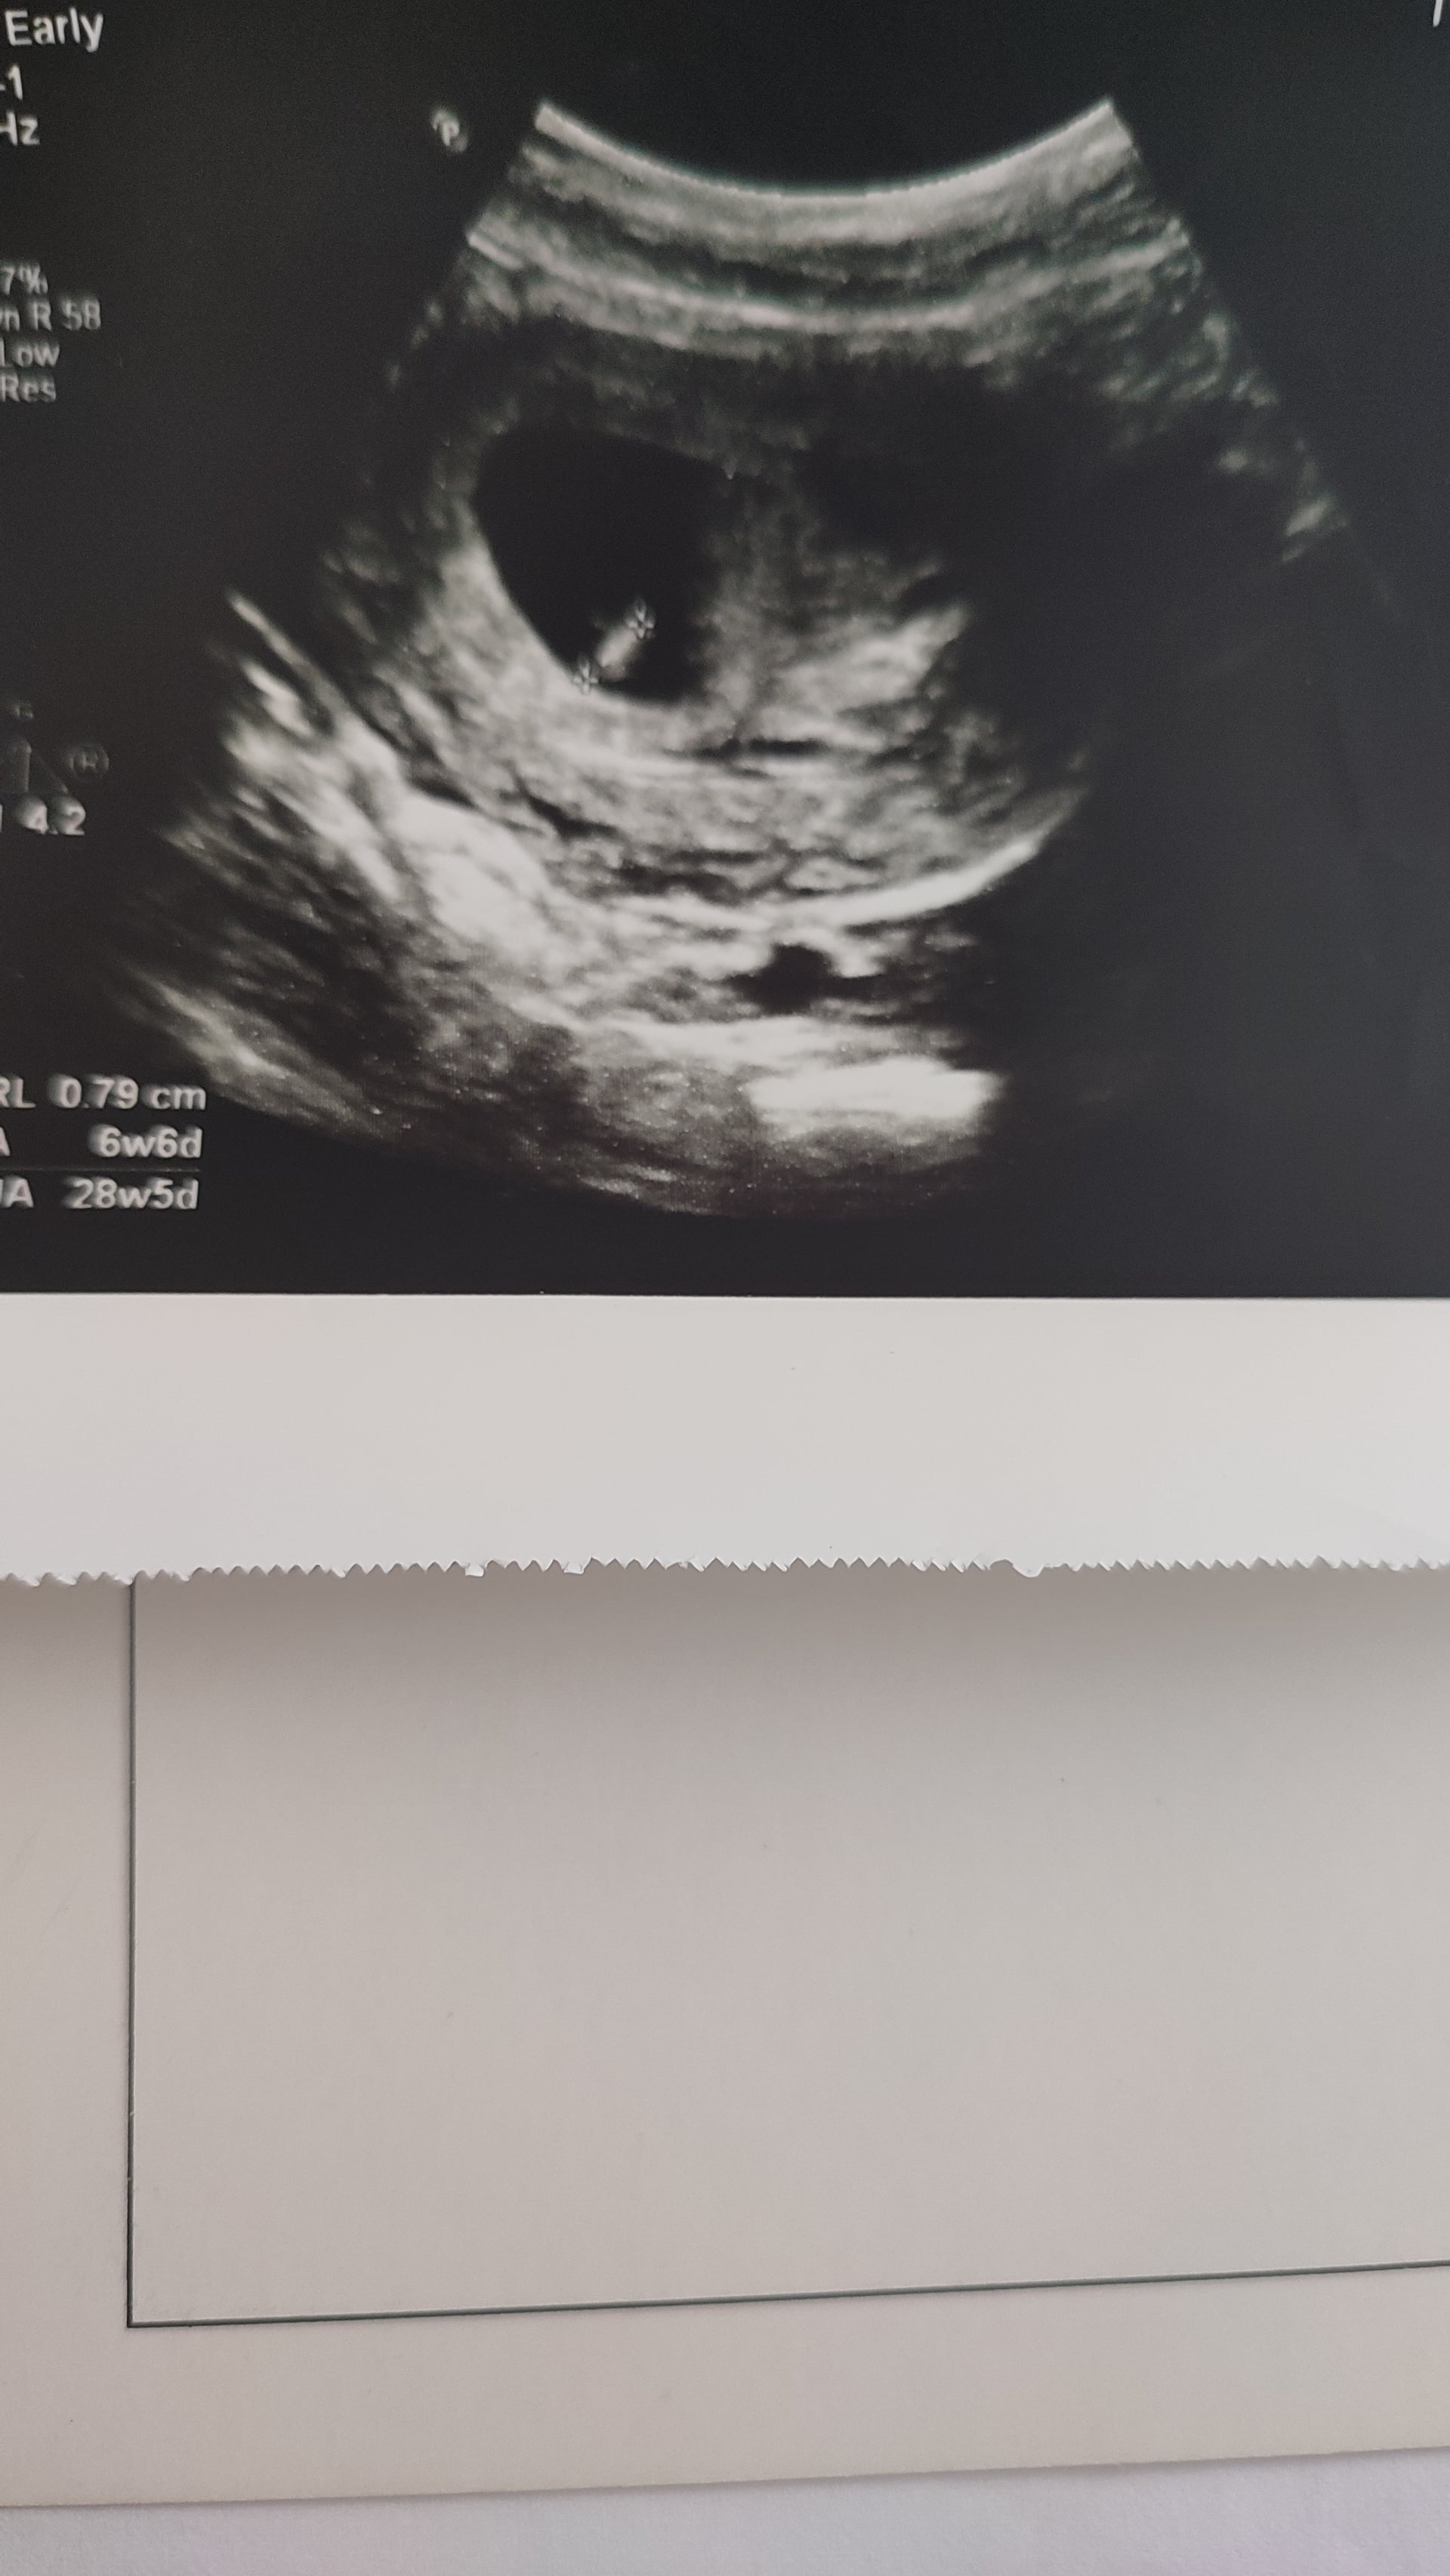

Bu usg 6 haftalik henuz sanirim yeni ultrason fotosu varmi

Nub olayından hiç anlamıyorum ki :joy:

Bende cizdim erkek gibi geldi ustte cikinti nub olabilir die ama baska biryerde net kiz bu diyenler olmus doktorda kiza benzetti gbi

Nub öğrensek köşeyi döneriz :joy: